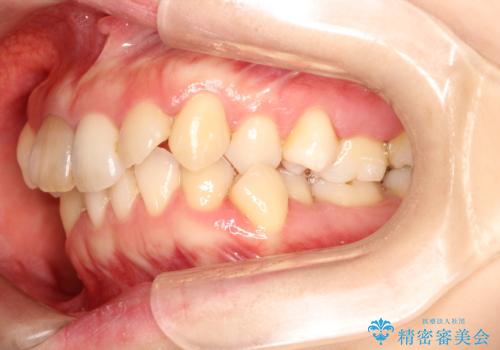

- 上下のがたつきを主訴に来院された患者様です。

上下の前歯と奥歯にがたつきがありました。

上下の奥歯を後方に移動させるのと、歯と歯の間をわずかに削ることでスペースを作り、歯を並べる計画としました。